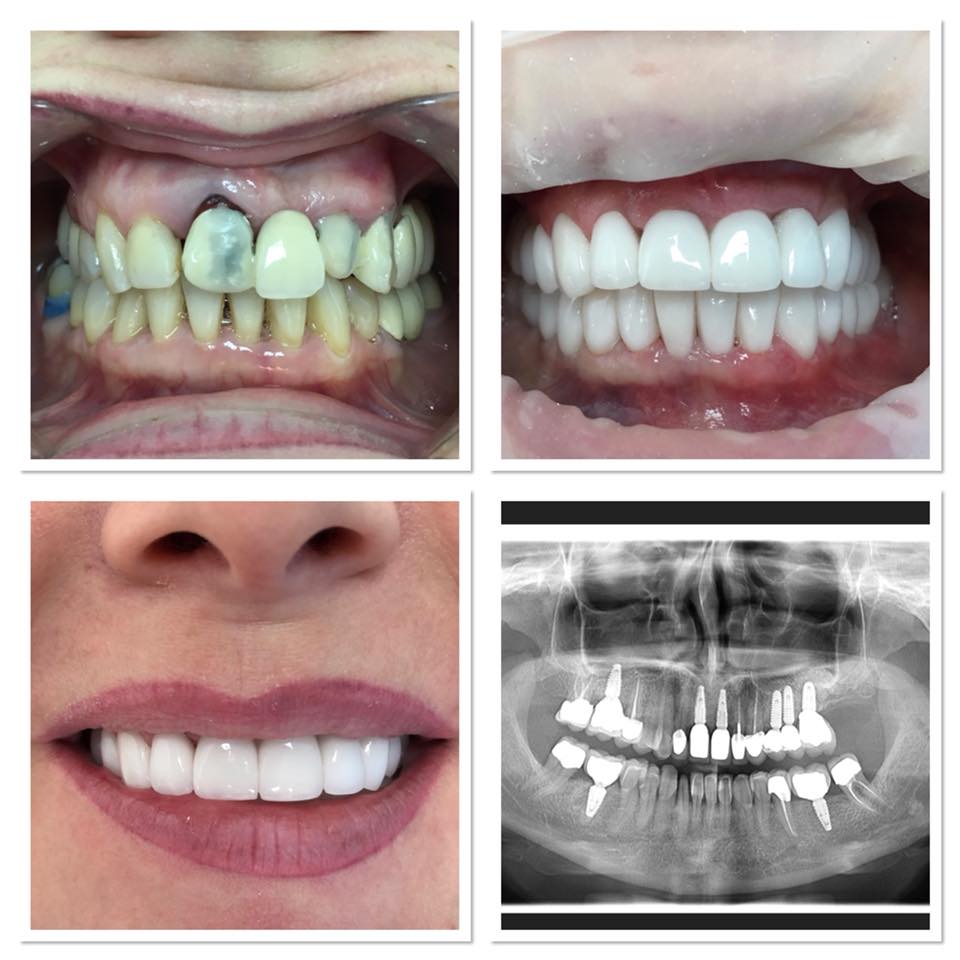

Реставрационное покрытие

Реставрационное покрытие 107 фотографий